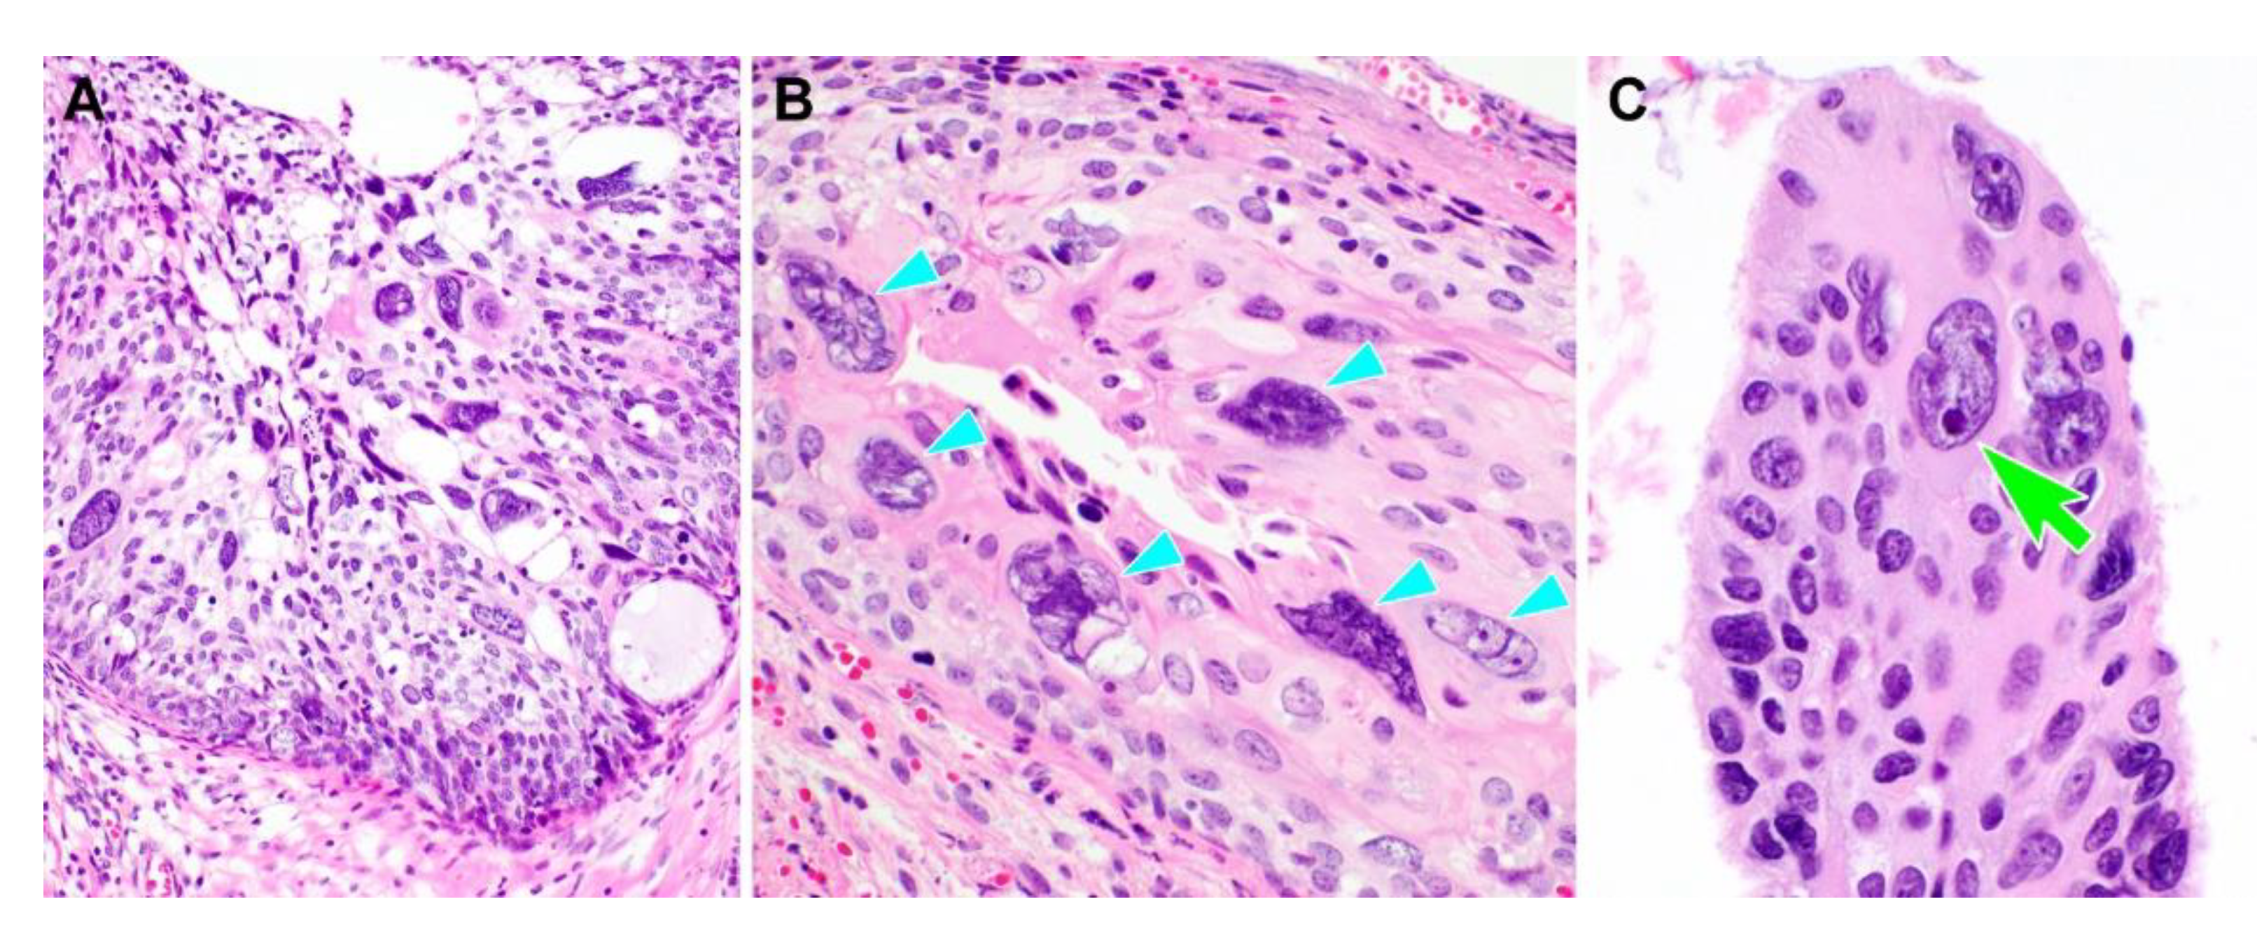

3.2. Pathological Characteristics